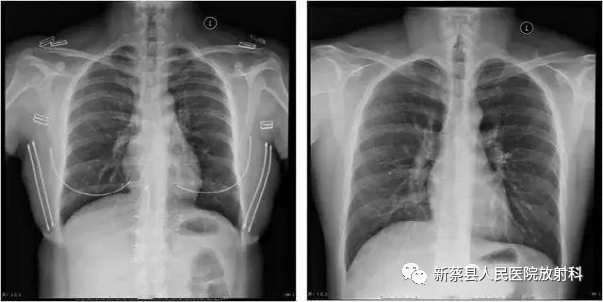

对于拍X光片人们通常存在着四种误区,即认为放射线对人体有伤害,坚持生病了也不拍片;不是金属不碍事;人体的两个侧面都要照;站着拍和躺着拍效果一样。医生提示,拍X光片是最常见的一种影像学检查,大家不必对此产生误解。

误区一:放射线对人体有伤害,坚持生病了也不拍片

据医生介绍,胸部正位摄片时接受的X线照射剂量为0.12mSv,约为造成人体损伤的单次最大接受剂量的1/20000,所以说,一次普通的X线摄片检查,对人的危害程度并不大,无需过多担心。“人们常说药有三分毒,任何一种药都有不良反应和毒副作用,但是只要正确用药并掌握它的用量,就能发挥药品的最大作用,从而为患者服务。”医生举例说,如晒太阳可以从中获取维生素D,但是皮肤过多的暴晒就会导致皮肤癌;此外,生活中也有很多的电器是有辐射的,难道我们就弃之不用吗?关键是要怎样用的问题。

误区二:不是金属不碍事

随着大众文化水平及对医疗知识的不断提高,人们逐渐认识金属及高密度物品会阻碍X线的穿透,如金属纽扣、项链、玉佩、文胸等,患者一般都会配合医生将其去除,但类似护膝、膏药、棉被及衣服上的油漆图案等,都会对X线的穿透造成影响,甚至在X光片上留下影像,从而给医生的诊断带来了困难。如患者王小姐,带着感冒发烧的小宝宝拍X光片,因担心脱掉毛衣会令小宝宝的感冒加重,王小姐说什么也不肯脱掉宝宝的衣服。使本来就难以诊断的小孩胸片,又因为几件毛衣的干扰留下了重重伪影,结果只能重照了。

误区三:人体的两个侧面都要照

我们通常所用的照相机如果拍左边面部就看不到右边。但是X光不一样,它具有穿透性,看清内部实质性内容。因此,如果是拍四肢骨和脊柱是一个侧位就可以了。这不像肺分为左肺和右肺,所以一旦哪边有问题就得哪边靠片,目的就是使病变侧能更清晰地显示在X光胶片上,以减少放大。如李先生不小心摔伤了小腿右侧,到医院拍片时医生只拍了一个侧位,李先生认为另一侧没有拍到,坚持要加拍另一侧。

误区四:站着拍和躺着拍效果一样

站着拍和躺着拍出来的效果没有分别,这是种误解。以胸部照片为例,站着拍的目的可以在重力的作用下使心影自然,在大口吸气时可以使肺部扩张,前胸靠片可以减少心脏的模糊、减少心脏的放大率,且可因投照距离的增大使两侧肩胛骨投影在肺野之外并减少胸部的放大率。而躺着拍时就达不到这种效果。因此,该站着拍时,患者应该坚持站着,即便在亲友的搀扶下也要站着或坐着拍。当然,在危及生命时就要灵活变通了。